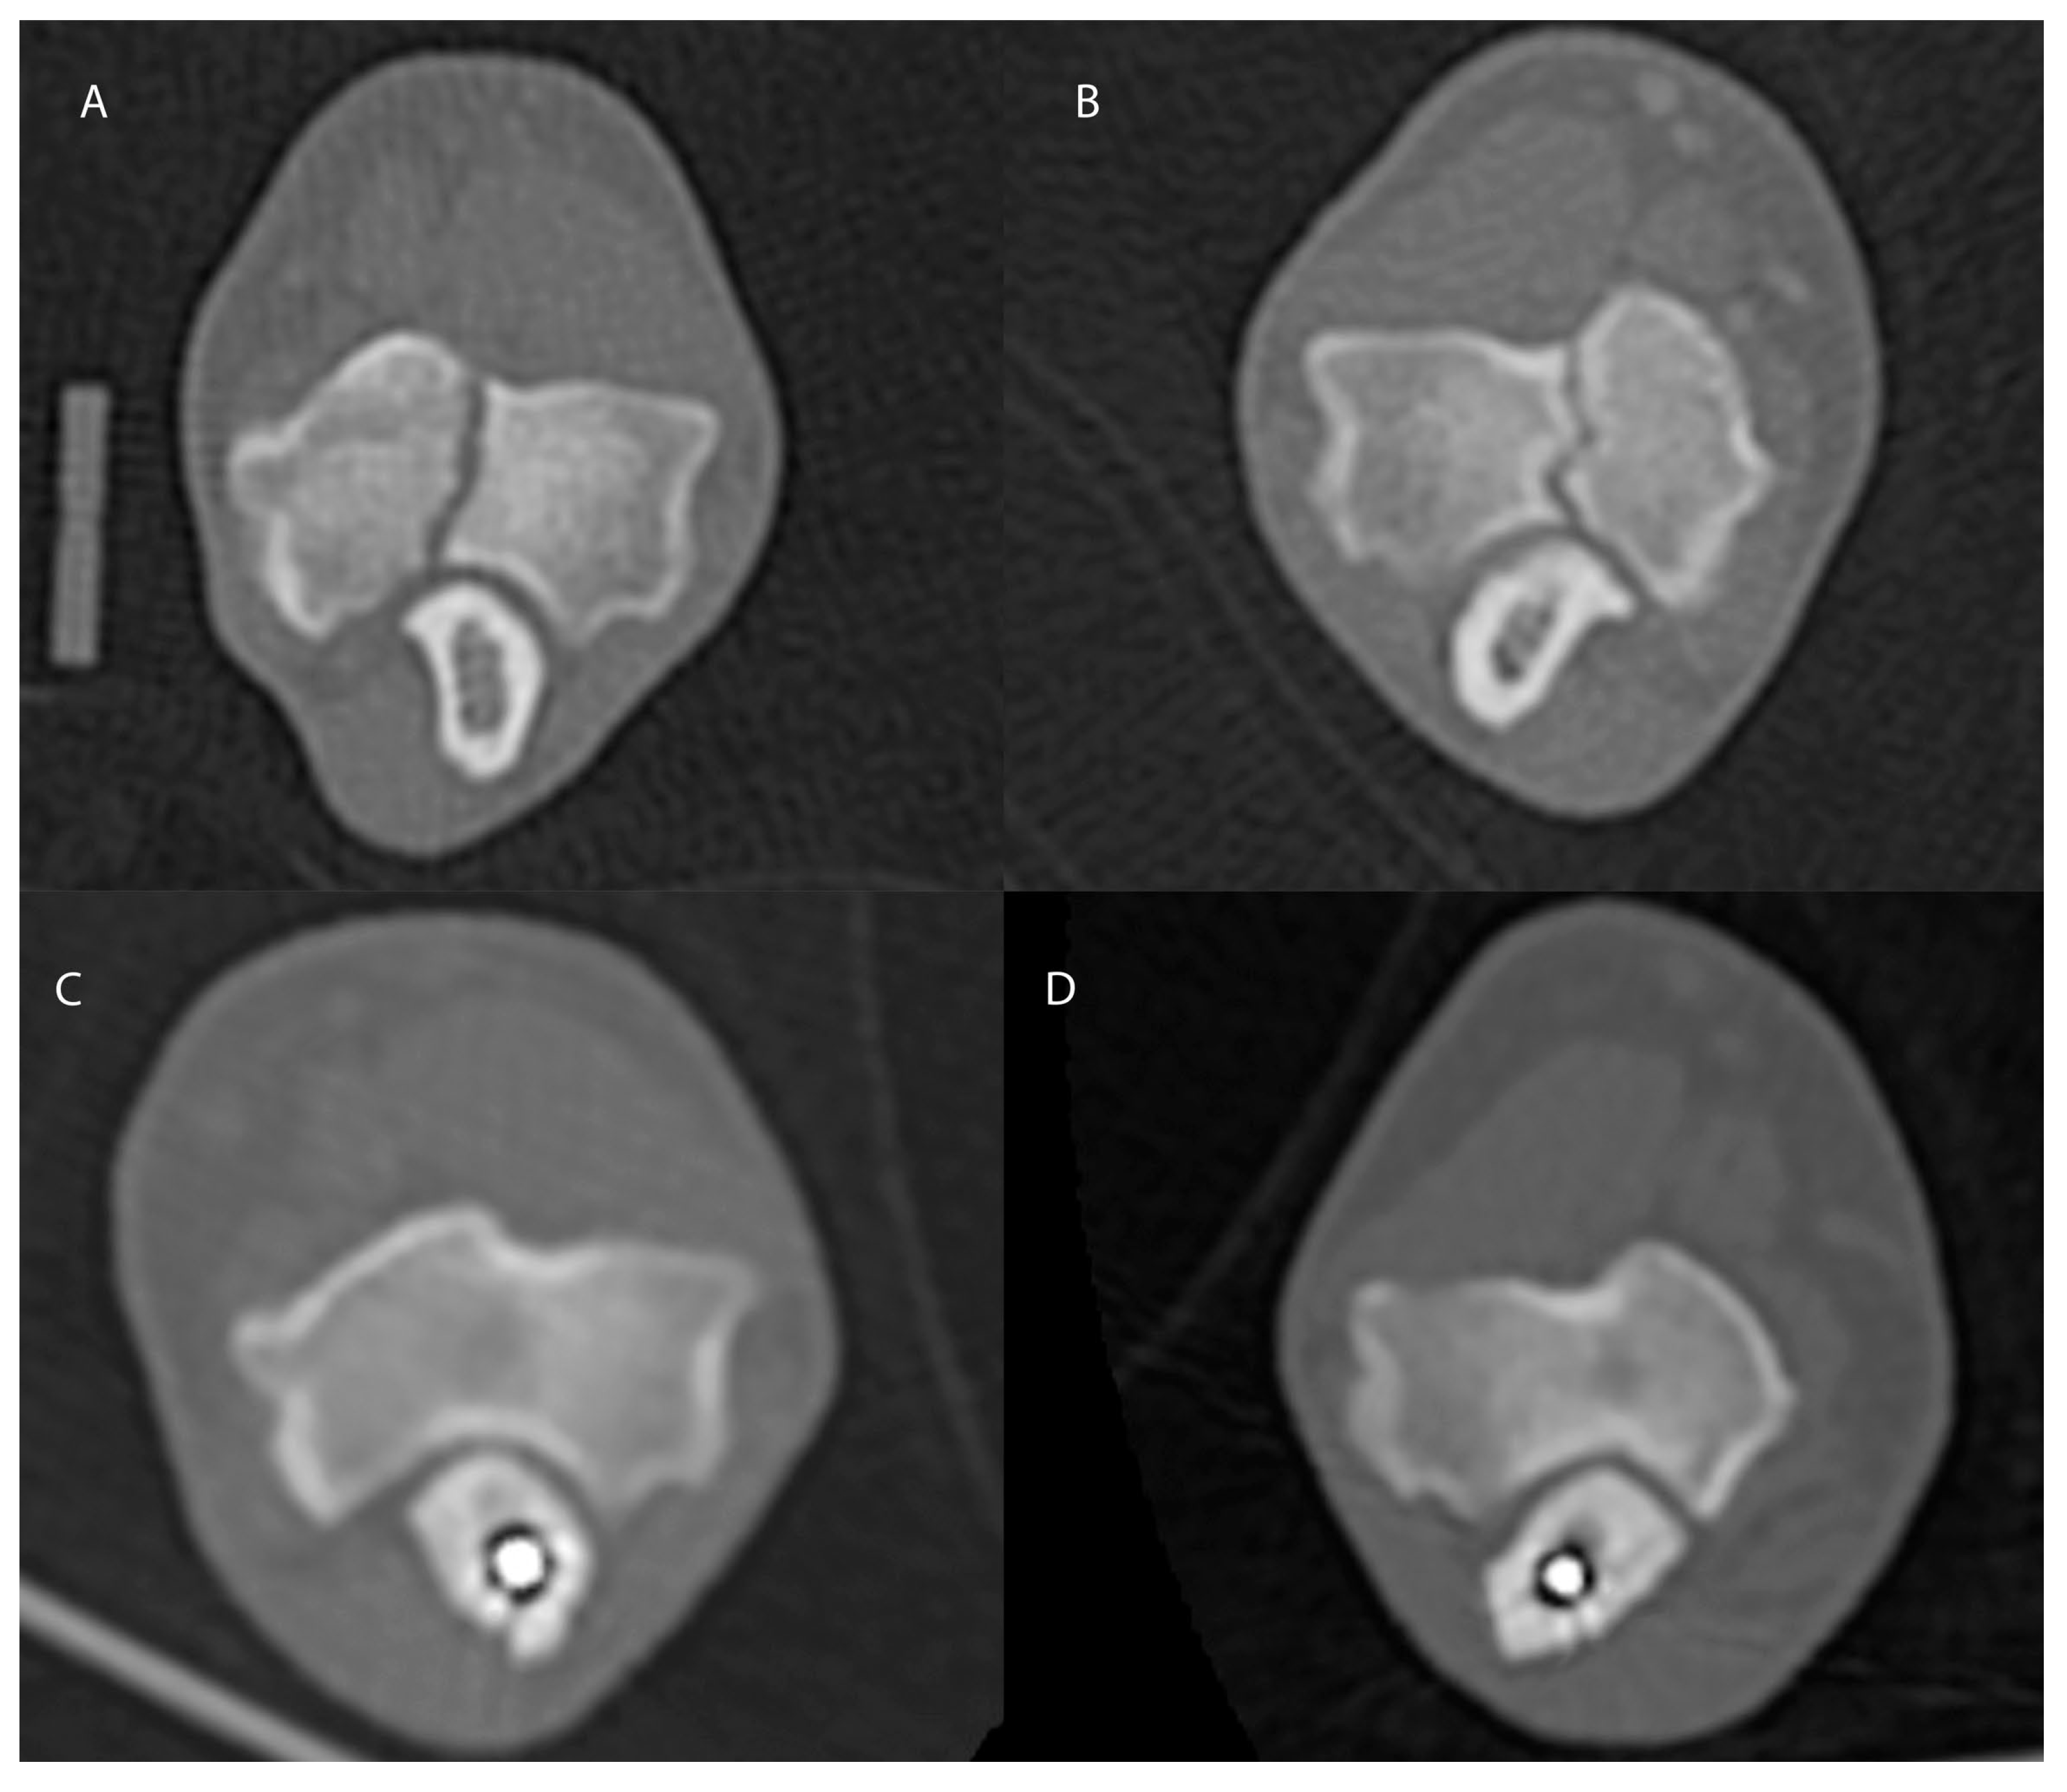

2. Materials and Methods

Surgical Treatment

3. Results